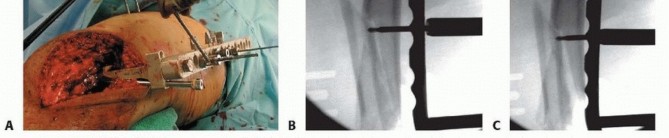

### TECH FIG 2 • AP radiograph (A) and scanogram (B) showing that length was reestablished with the external fixator. The rotation should be checked once again before locking the external fixator construct, as described earlier under Positioning. The same technique should be performed under sterile conditions. Varus-valgus alignment should be assessed before final tightening as well. This can be done by using the Bovie cord intraoperatively and assessing the mechanical axis of the limb by fluoroscopically evaluating from the hip to the ankle with the cord centered at the femoral head all the way to the ankle. The point at which the cord crosses the knee allows one to judge the varus-valgus alignment. 2. ## Open Reduction and Internal Fixation of the Distal Femur with Locking Plates (Type C Fractures) This technique can be used regardless of the locking plate system used. Each system's technique guide should be reviewed before use as each system has its own idiosyncrasies. Variations in plate application as well as reduction tools and techniques are unique to each system. The temporary external fixator is prepared using a “doubledouble” technique. The fixator is first prepared with a Betadine “scrub” (7.5% povidone-iodine) solution followed by a Betadine “paint” (10% povidone-iodine) solution (Beta-Beta preparation), followed by the extremity with a second Beta-Beta preparation. The surgeon then does an alcohol preparation, followed by iodine for the fixator, followed by alcohol and iodine on the skin. This has been successful in our practice and allows for maintenance of traction during the preparation and aids in the actual surgery, functioning as a femoral distractor. (Chlorhexidine is used in iodine- allergic patients.) An alternative is to completely remove the fixator components, except the pins, and wash, sterilize, and then reassemble the fixator on the patient after the leg has been prepared. If there is no temporary bridging external fixator, the metaphyseal component of the fracture can be reduced and brought out to length with a femoral distractor, a temporary simple external fixator, or manual traction if adequate help is available. Rotation of the proximal segment can be manipulated with the device used. 480 ### Midline Approach with an Extended Lateral Parapatellar Arthrotomy A straight incision is made directly anterior about 5 cm proximal to the superior pole of the patella and distally to the level of the tibia tubercle ( TECH FIG 3A). The lateral skin flap is developed to allow for a lateral parapatellar arthrotomy ( TECH FIG 3B). The arthrotomy is performed, ensuring a cuff of tissue on the lateral aspect of the patella for repair as well as medially on the quadriceps ( TECH FIG 3C). The patella can be subluxed medially or inverted with knee flexion to allow exposure of the condyles ( TECH FIG 3D). Additionally, a blunt Hohmann retractor can be placed on the medial side at the level of the condyle to retract the patella. The capsule is subperiosteally elevated off the lateral femoral condyle to allow for placement of the plate. The lateral collateral ligament is preserved because the dissection is limited to the anterior two-thirds of the lateral femoral condyle and plate placement is usually proximal to the lateral epicondyle. The medial side in the metaphyseal region is left undisturbed as much as possible.

TECH FIG 3 • Patient with grade II open distal femur fracture (also shown in FIGS 5D-F, 6B, and 7). A. Straight midline incision. B. Lateral skin flap is developed. C. Arthrotomy is started and then extended proximally into the quad tendon (dashed line). D. The arthrotomy is completed and the condyles are visualized with medial subluxation of the patella. ### Reduction of the Articular Surface The joint is evaluated to determine comminution. Joint reconstruction is then performed with direct reduction. Each condyle is fully assessed first for smaller fracture fragments, with the goal of restoring each condyle anatomically. Small-diameter screws ( <3.0 mm) may be used and can be countersunk underneath the articular surface. Large coronal fracture fragments are best treated with countersunk 3.5- to 4.5-mm lag-type screws. We use headless screws. Once each condyle is thought to be restored, or if a simple fracture pattern is present, the condyles should be reduced to each other using a large, pointed reduction forceps ( TECH FIG 4A-C). Each fragment can be rotated relative to another; this must be addressed as discussed before. The best way to assess this is under direct visualization and evaluating the reduction at the trochlear region of the patellofemoral joint. Additionally, preoperative evaluation assessing the lateral radiograph can guide the surgeon. Intraoperative fluoroscopy to reassess the lateral view is also useful. Temporary Kirschner wires or the guide pins for the locking screws for the plate can be used for additional stabilization of the two condyles ( TECH FIG 4D). 481

### TECH FIG 4 • The condyles are reduced under direct visualization (A) and confirmed with AP (B) and lateral (C) intraoperative fluoroscopic images. D. Guide pins through the plate template or screw trajectory guide are used to temporarily stabilize the intercondylar split. - Definitive Fixation of the Condyles This can be accomplished outside the plate first and supplemented with screws through the plate. The area around the proposed plate, the “periphery,” can be used for the screw placement to avoid interference with the plate placement itself. If this is done, then the metaphyseal fracture does not necessarily have to be properly reduced before initial screw placement. Screws can also be placed from medial to lateral to avoid interference with the plate. Definitive fixation can be accomplished through the plate also (see next section on Screw Placement). If this is done, the metaphyseal component should be reduced to ensure the proper flexion-extension alignment of the shaft with the condyles. This will ensure that the plate is collinear with the shaft once fixed to the distal segment. Otherwise, a malreduction in the sagittal plane will occur. The temporary Kirschner wires can be left in place to stabilize the joint. ### Reduction of the Shaft to the Distal Segment Once the articular surface is temporarily stabilized or reduced, the reduction of the shaft to the distal segment should be performed before plate application. This can be temporarily stabilized with Kirschner wires or Steinmann pins. Alternatively, precisely placed bumps underneath the distal segment can be used to correct the extension of the distal segment and align it with the shaft. Adjustment or loosening of the temporary external fixator can aid in reduction if needed. The plate can then be placed submuscularly. ### Placement of the Plate Each fixed-angle plating system is designed to help reestablish the valgus alignment of the distal femur. The screws in the distal portion of the plate are designed to be parallel to the joint surface. Thus, the initial guidewires for these screws should be placed parallel and confirmed by fluoroscopy. A distal “joint wire” can be placed to better evaluate this ( TECH FIG 5A). Placing the distal screws parallel to the joint will help ensure that when the shaft is brought to the plate, the anatomic axis of the femur is restored. With the variable-angle locking plates, the same technique should be employed to ensure that the plate is applied in a way to restore the anatomic axis of the femur. A fixedangle central screw hole still exists in these plates to aid in plate application ( FIG 11C, parallel lines; FIG 11D, red arrow/red circle). A distal screw trajectory guide is provided for some systems ( TECH FIG 5B). This can be used to help ensure accurate placement of the plate distally, and initial guidewires can be placed through this. Once the wires are placed, the guide can be removed and replaced with the plate using the wires as a guide. However, the shaft portion of the plate requires submuscular insertion, and thus the plate cannot be brought to an appropriate position to allow this to occur. 482

### TECH FIG 5 • A. Distal reference pin is placed to ensure that the proximal pin is parallel to the joint. B. Clinical picture depicting the guide. C. Different patient showing the penetration of the medial side with the guidewires to allow plate placement. D,E. The plate is placed with additional guide pins in place. - F,G. Lateral intraoperative fluoroscopic images ensure proper plate placement on the femur before screw insertion. To solve this, the guidewires can be driven through the medial side of the knee, which is distal enough to be safe ( TECH FIG 5C). The plate can then be inserted submuscularly and the guidewires driven back through the plate laterally, thus aligning the plate to the distal segment and ensuring proper screw trajectory and plate placement ( TECH FIG 5D,E). A single guidewire in a central hole will still allow flexion-extension placement of the plate if this needs to be adjusted. After placing the initial guidewire parallel to the joint distally, and ensuring the fracture is reduced, the surgeon should obtain fluoroscopic visualization of the plate proximally on the shaft to ensure that the plate is on the bone ( TECH FIG 5F,G). To ensure placement of the plate on the bone both proximally and distally, it is best to stabilize the plate distally 483 (where exposure is) using a guidewire in the center hole. This allows for a pivot point around which the AP positioning of the plate can be manipulated for the shaft. Fluoroscopy to image the lateral is then used to ensure placement.